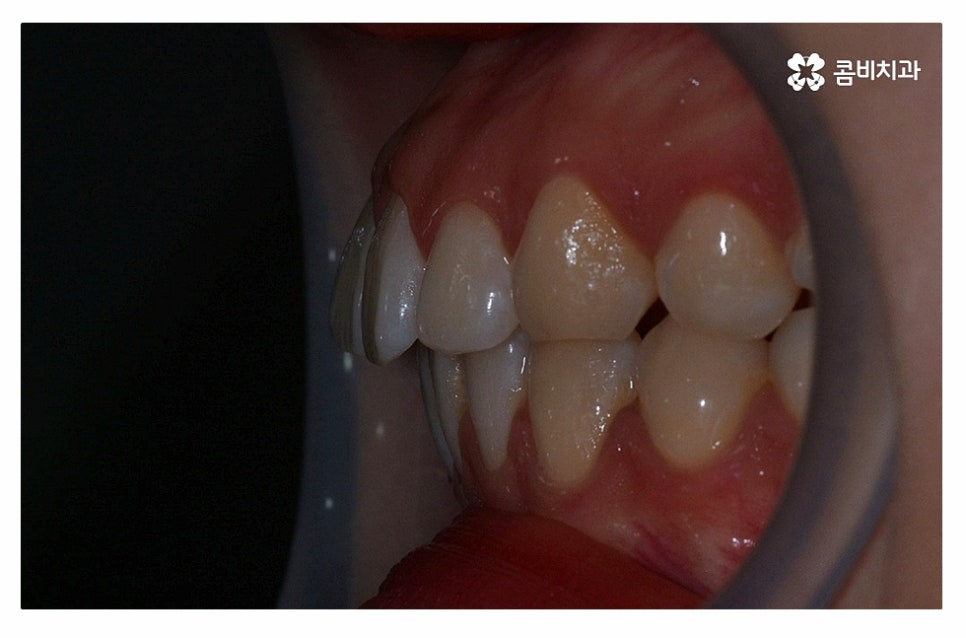

위 환자분의 경우 정면에서 보이는 치열은 가지런한 편이지만

치아가 돌출되어 돌출입으로 고민했던 사례이며

치아의 이동 공간 확보를 위해 발치 교정을 진행한 사례라고 할 수 있어요.